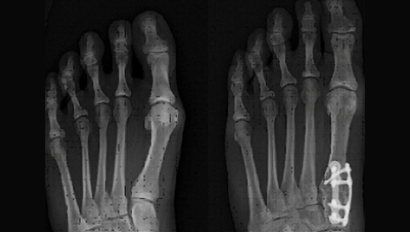

Bunion (Hallux Valgus)

• Depending on the amount of deformity Dr. Marsh may fix the deformity minimally invasively through a MICA chevron osteotomy, open chevron or scarf osteotomy or a Lapidus midfoot fusion